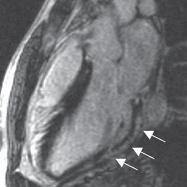

Miocarditis

Las miocarditis encuadran un grupo de entidades patológicas en las que los microorganismos infecciosos y/o un proceso inflamatorio causan una lesión en el miocardio.

Clínica

La presentación clínica es muy variable ☤:

- Puede haber fiebre o antecedente de viriasis 7-10 días antes.

- Suele asociarse a pericarditis vírica (miopericarditis), predominando la clínica de la pericarditis.

- Insuficiencia cardiaca: por disfunción ventricular secundaria a la infiltración inflamatoria del miocardio.

- Arritmias: muerte súbita (por arritmias ventriculares) o sincope (por bradiarritmias).